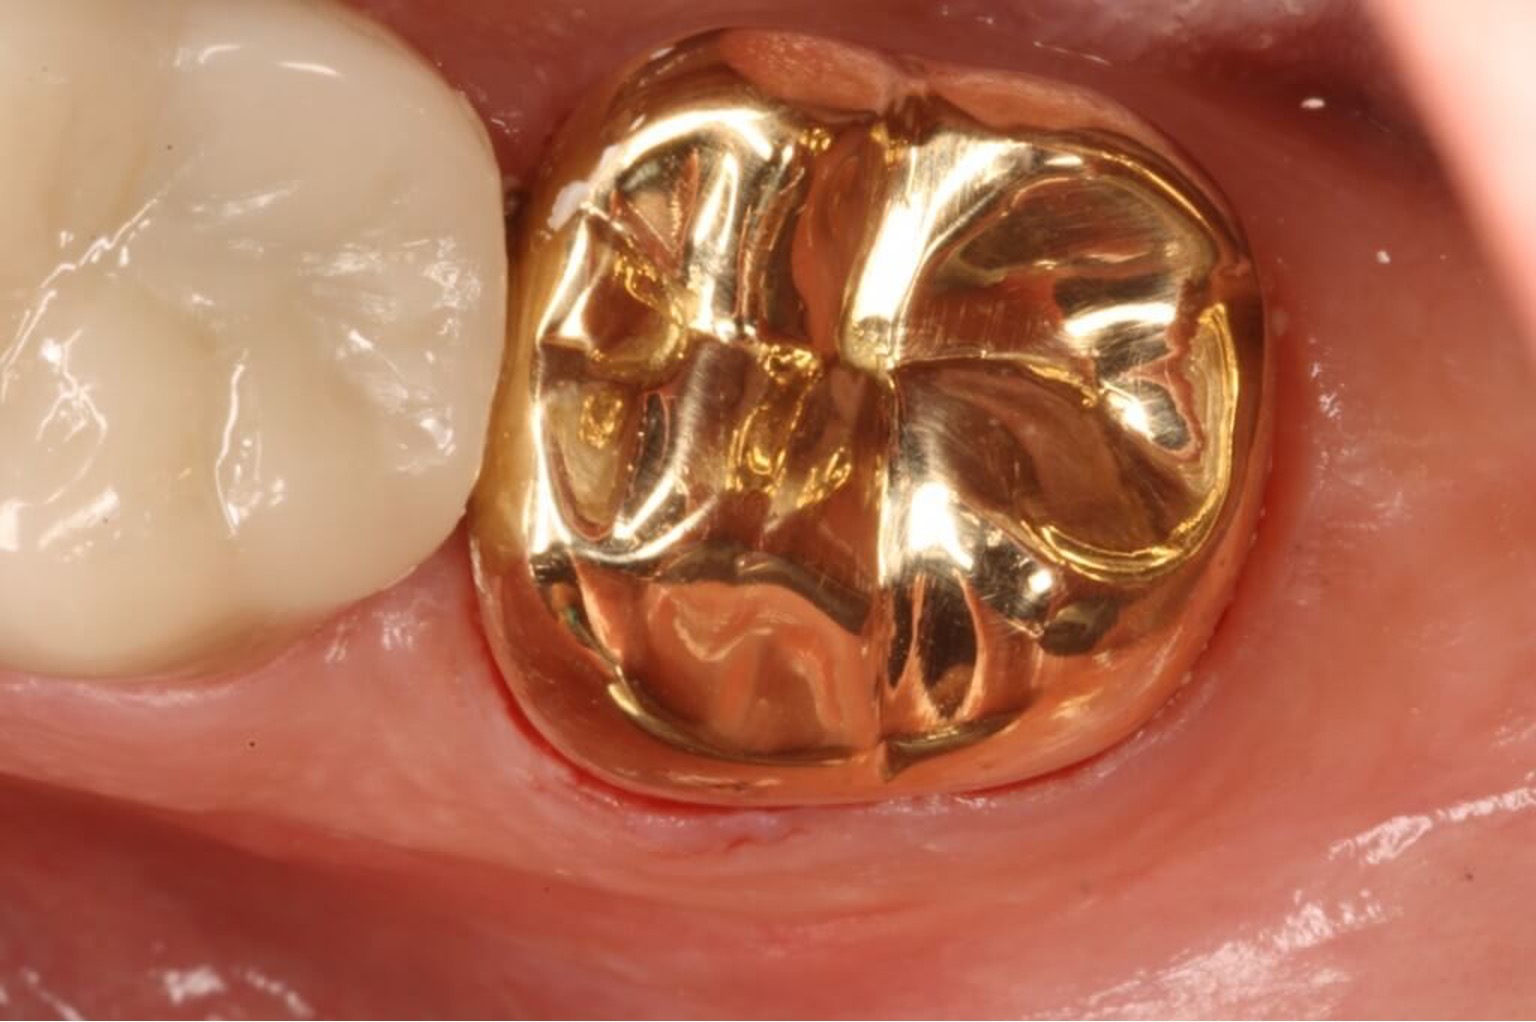

Gold crown is also known as Royal crown. These are caps made of gold alloy or gold-plated materials used to cover a damaged tooth offering superior strength and a perfect fit. Gold crowns are a preferred choice for patients seeking a premium dental restoration that provides unmatched longevity and stability. Ideal for molars and back teeth, gold crowns ensure optimal functionality while withstanding heavy chewing forces.

Now a days, mostly patients ask to the dentist to put them on front teeth as a fashion because of outstanding value an. Gold has been historically favored for its durability and biocompatibility in dentistry. These are ornamental headpieces typically made of gold and precious gems, worn by monarchs during ceremonies to symbolize power and authority. These crowns are made from high-quality gold alloy, if you're looking for a reliable and durable solution for your dental needs, gold crowns offer outstanding value and performance.

Gold crowns, known for their unmatched durability and biocompatibility, cost between Rs. 90,000 to Rs. 200,000 in Lahore.

Gold crowns are more expensive because Gold and gold alloys used in these crowns are costly.

• Longevity and Biocompatibility: Gold is one of the most durable materials, and its biocompatibility makes it ideal for patients with sensitivities.

• Fitting and Craftsmanship: The high quality of gold crowns requires precise fitting, which can increase the overall cost.

Gold crowns are perfect for patients seeking a long-term solution with exceptional strength and reliability, especially for back teeth.